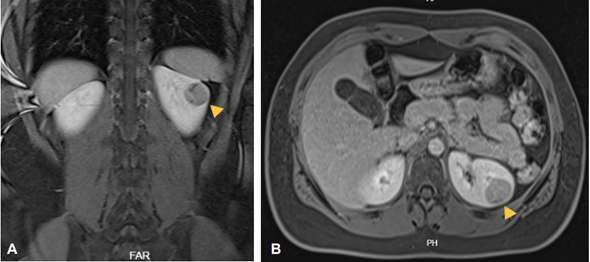

Se solicitó resonancia magnética nuclear (RMN) de abdomen contrastada que reportó una lesión nodular y sólida en el riñón izquierdo, heterogénea, ligeramente hipointensa en los pulsos T2, en T1 con algunas áreas de señal líquida local, con bordes definidos y aproximadamente 27x22 mm en el plano axial, con refuerzo progresivo de la lesión tras la administración del contraste endovenoso, sin compromiso de estructuras adyacentes (Figura 1).